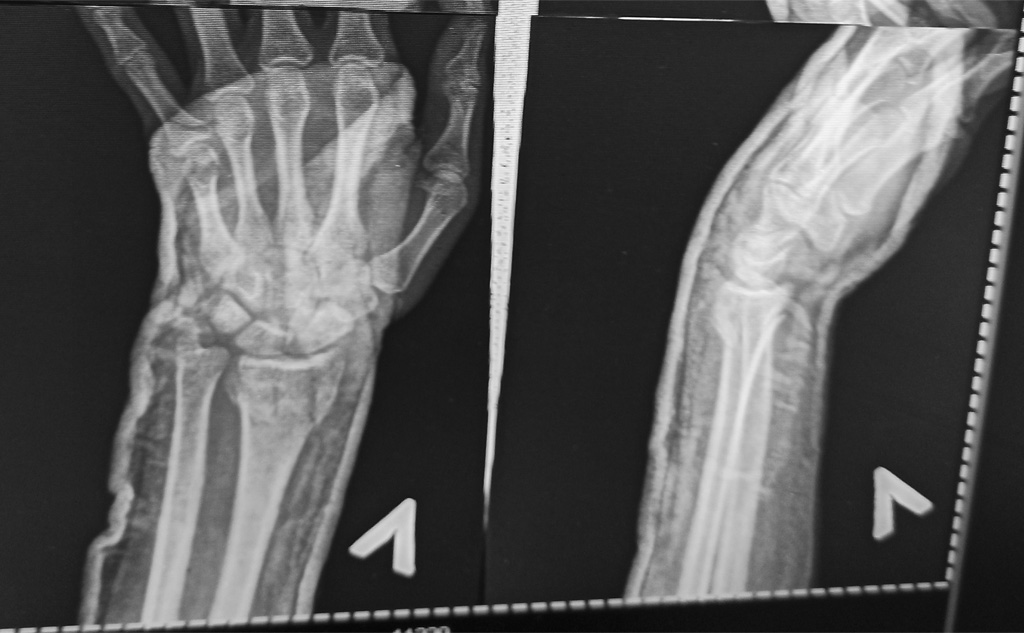

Смещение после закрытой репозиции переломов обеих лучевых костей со смещением + перелома шиловидного отростка на правой руке. Допустимое смещение, или нужно делать открытую репозицию?

Уважаемые специалисты, прошу Вашего экспертного мнения.28.08.2020 после неудачного приземления получил травму обеих рук.29.08.2020 обратился в ближайший травмпункт, по результатам рентгена - перелом обеих лучевых костей со смещением + перелом шиловидного отростка на правой руке.Выполнена закрытая репозиция.Наложен гипс (чуть ниже локтя).03.09.2020 контрольный рентген.Врач, который же и делал репозицию - сказал, есть небольшое смещение, но идеально совместить осколки все равно не получится. Смещение допустимое, ничего страшного.Сказал приходить через месяц.Гипс оставил тот же самый.Сейчас самочувствие хорошее, даже вот могу немного печатать на клавиатуре. Только при разгибании больших пальцев есть дискомфорт и боль, и при усилии нажатия (напр. когда надо вилку вставить в розетку). Сустав стараюсь не крутить.Однако начитавшись про последствия неправильного сростания костей, меня терзают сомнения.По-вашему, всё нормально и можно спокойно долечиваться в гипсе, операция не нужна?Какие могут быть долговременные последствия такого смещения?Рентген от 03.09.2020 (5 дней после репозиции) прилагаю:https://drive.google.com/drive/folders/1isOdNQyIx0iE-neLqHW7Ddx1X2zg1MjQ?usp=sharingБольшое спасибо за Ваше доброе дело, долгих лет Вам.

Есть небольшое смещение. По возможности лучше бы его устранить, иначе может быть небольшой дефицит сгибания в лучезапястном суставе.